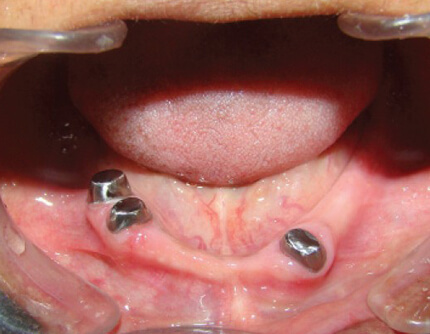

The dentures are nothing but artificial teeth that are meant to replace missing teeth, and are placed on or balanced on the other teeth in the mouth. They are known as hybrid dentures or tooth-supported dentures. These dentures differ from overdentures where in the former is held in place by adhesives and in the latter they are supported by screws that are driven in to titanium dental implants that in turn rest on your jaw bone. However they look to be the same from the outside. These overdentures are made from acrylic, metal and some other durable materials.

Fixed Vs Overdenture: Both of them provide a crown and an artificial gum tissue. The only difference is that the former cannot be removed and the latter can be replaced and removed. The various types of dentures are full dentures, partial dentures and temporary dentures. The two types of dentures are complete and partial. The former is used when there are absolutely no teeth and the latter is used when there are some teeth in the mouth. Some advantages of overdentures are stability, ease of eating and talking, bone retention.